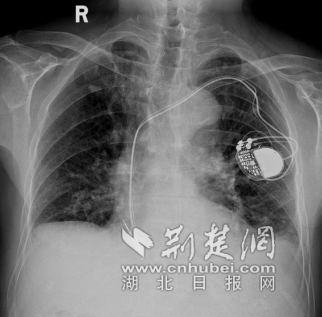

双腔起搏器已植入罗爹爹心腔内 通讯员供图

1月4日,手术如期进行。术中,杨新玮博士凭借娴熟的技术和细致的操作,成功经静脉血管将起搏电极精准植入罗爹爹心脏的理想位置,并妥善固定了起搏器装置,手术历时1个半小时顺利结束。术后,罗爹爹的心跳即恢复了正常,不再“慢动作”,精神状态也明显得到好转。“根据目前植入罗爹爹心腔内起搏器工作的情况,只要保养得当,是完全可以使用5到10年的,帮助他安然度过百岁。”杨新玮博士说。